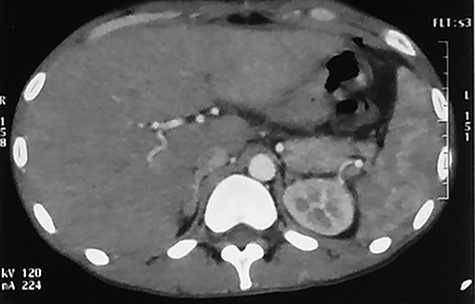

The post-operative status was marked by the persistence of SIRS, a deterioration of general appearance, pain in the right hypochondrium and hepatomegaly noticed on the eighth post-operative day. No jaundice was noted. A contrast-enhanced abdominal CT scan was performed showing small, homogeneous hypodensities disseminated in the liver parenchyma giving the appearance of miliary abscess. There was no lymphadenopathy or associated ascites (Fig. 1).

Abdominal CT injected at portal phase performed on 10th postoperative day showing millimetric, homogeneous hypodensities disseminated in the hepatic parenchyma.